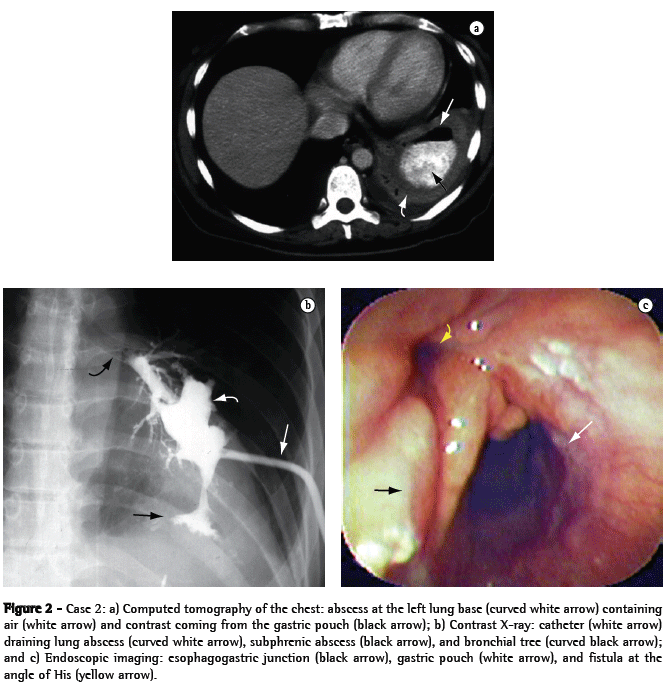

A 44-year-old male patient who underwent Fobi-Capella surgery by laparoscopy in order to control morbid obesity underwent a second operation 48 h later to relieve intestinal obstruction. Two months later, two endoscopic balloon dilatation sessions were carried out in order to correct stenosis of the gastrojejunal anastomosis. Subsequently, the patient presented projectile vomiting, productive cough, fever, and pain in the left thoracoabdominal region upon deep breathing, and a nodule of 7 cm in diameter was detected in the left lung base through computed tomography of the chest (Figure 1a). The patient presented clinical improvement after antibiotic therapy, respiratory therapy, and monitoring in the pulmonology department. However, there were two recurrences within an interval of three months, at which point a gastrobronchial fistula was diagnosed through X-ray (Figure 1b) and endoscopic (Figure 1c) imaging, which revealed an opening of 10 mm in diameter at the angle of His, through which it was possible to pass the endoscope until it reached a small subphrenic cavity where an internal opening of the fistulous pathway toward the bronchial tree could be seen. The attempt at correction via laparoscopy was unsuccessful, and the only procedure carried out was a gastrostomy (for the purpose of nutrition) in the excluded stomach. Using an electric scalpel, we performed endoscopic section of the gastric stenosis and of the septum located between the fistula and the gastric pouch, together with balloon dilatation (20 and 30-mm balloons; Boston Microvasive, Boston, MA, USA), and clips were used in order to close the fistula (Olympus Corp., Tokyo, Japan). Six months later, we observed an increase in the diameter of the gastric pouch, the disappearance of the abovementioned septum, and the definitive closure of the fistula, which resulted in the resolution of the lung abscess.